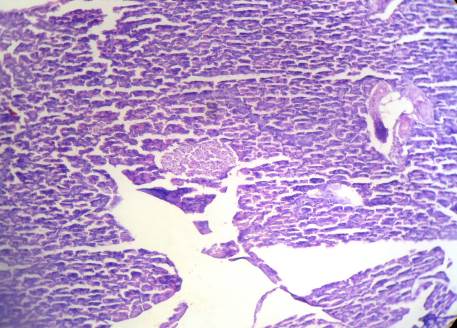

Group III: Positive Control (Alloxan monohydrate+Glipizide)

Fig. 10: The numbers of islets cells were mildly decreased, islets cells were mildly swelled